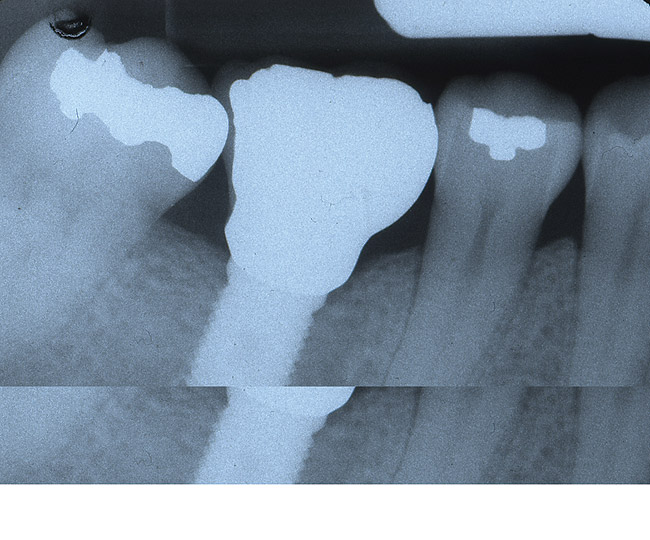

Figure 2a  A periapical radiograph of the tooth revealed the presence of a radiolucent appearance that was more significant at the midroot level. A root fracture was evident after flap elevation.

Figure 2a

The patient was a 65-year-old healthy man who was referred for a periodontal evaluation of tooth No. 28. The patient presented with the chief complaint of pain and swelling in the lower right side of his mandible. Clinical examination revealed deep probing depth primarily (9 mm) on the distal-facial aspect of tooth No. 28. The tooth presented with grade 2 mobility. A periapical radio­graph of the tooth revealed the presence of a radiolucent appearance that was more significant at the midroot level (Figure 2A). The prognosis was determined to be "hopeless" because of a root fracture.